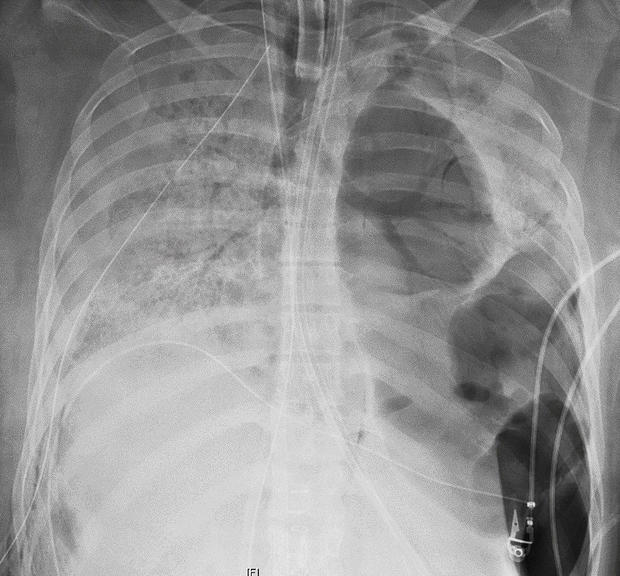

Хирург Анкита Бхарат, которая проводила операцию, сообщила, что легкие девушки были все в дырах и практически слились с грудной клеткой.

Слева - здоровые легкие, справа - легкие пациентки из Чикаго